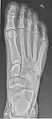

- دست - DP و مایل

پروجکشن دست چپ به واسطه dorsoplantar

پروجکشن جانبی

پروجکشن مایل